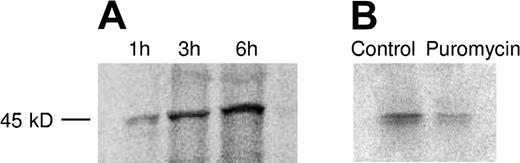

To confirm that there was an ongoing de novo synthesis of PAI-1 in platelets metabolic radiolabeling was performed. Following 35S-methionine incorporation for 1, 3, and 6 hours, immunoprecipitation was performed, which yielded a protein of the expected molecular mass of approximately 45 kD. The protein was detected both with the MAI-12 and PAI-1 (ab-1) antibodies. Figure 3A shows the results of the immunoprecipitation with PAI-1 (ab-1) of the 35S-labeled PAI-1. The increasing amount of radioactive PAI-1 over time confirms that there is an ongoing synthesis of PAI-1 in platelets. Following control immunoprecipitating without antibodies, no protein was detected (data not shown).

Metabolic radiolabeling and immunoprecipitation of platelet PAI-1. (A) Isolated platelets were incubated in the presence of 35S-methionine for 1, 3, and 6 hours. Platelet lysate and medium were immunoprecipitated with PAI-1 (ab-1) and the precipitated protein was separated with SDS-PAGE and subsequently examined by autoradiography. This yielded a protein of the expected molecular mass (approximately 45 kD), and the increasing amount of radioactive PAI-1 over time confirmed that there is an ongoing synthesis. (B) To inhibit protein synthesis, platelets were incubated for 6 hours in the presence of 1 mM puromycin, resulting in attenuated PAI-1 expression.

Metabolic radiolabeling and immunoprecipitation of platelet PAI-1. (A) Isolated platelets were incubated in the presence of 35S-methionine for 1, 3, and 6 hours. Platelet lysate and medium were immunoprecipitated with PAI-1 (ab-1) and the precipitated protein was separated with SDS-PAGE and subsequently examined by autoradiography. This yielded a protein of the expected molecular mass (approximately 45 kD), and the increasing amount of radioactive PAI-1 over time confirmed that there is an ongoing synthesis. (B) To inhibit protein synthesis, platelets were incubated for 6 hours in the presence of 1 mM puromycin, resulting in attenuated PAI-1 expression.

To inhibit protein translation, puromycin was added at a concentration of 1 mM. As shown in Figure 3B, this resulted in a partial inhibition of protein synthesis.